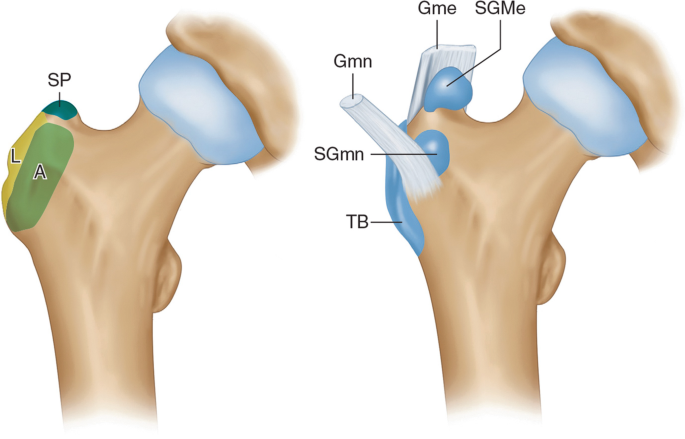

- Bursitis: Inflammation of bursae, small fluid-filled sacs that cushion joints, often affecting the shoulder or hip.

- Bursitis: Preliminary studies suggest acupuncture reduces inflammation and pain in shoulder bursitis, though more research is needed.

4. Shoulder Injuries (Bursitis or Rotator Cuff Strains)

Shoulder injuries cause pain and restricted motion. Key acupoints include:

- LI15 (Jianyu): At the shoulder, below the acromion. Relieves shoulder pain and improves mobility.

- SI9 (Jianzhen): On the back of the shoulder, near the armpit. Reduces stiffness and inflammation.

- LI16 (Jugu): Near the collarbone, above LI15. Promotes Energy flow to the shoulder.

- ST38 (Tiaokou): On the shin, below the knee. Distal point to relieve shoulder pain (TOM cross-body connection).

- GB21 (Jianjing): At the top of the shoulder, midway between neck and arm. Relaxes trapezius muscle and reduces tension.

Protocol: Treatment is 1-2 times weekly for 4-8 weeks, often with cupping to enhance circulation.